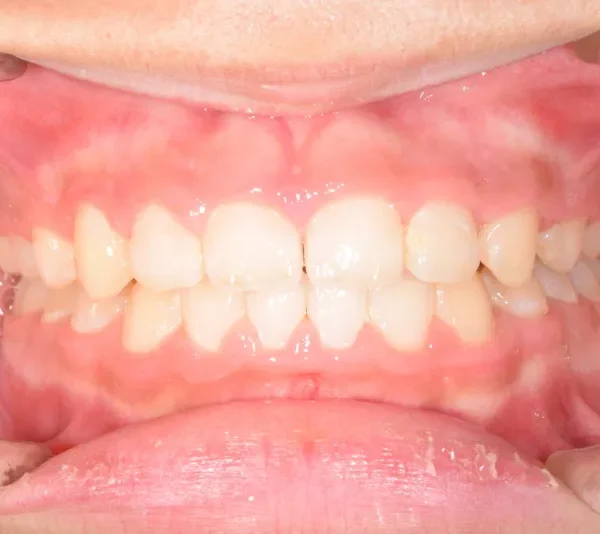

• 治療終了後

治療終了後

永久歯に生え変わってからはマルチブラケット装置を使用し、噛み合わせ・見た目をしっかり仕上げました。

治療回数42回、4年6ヶ月の治療期間で矯正治療を終了しました。

主訴が改善され、ご満足頂きました。